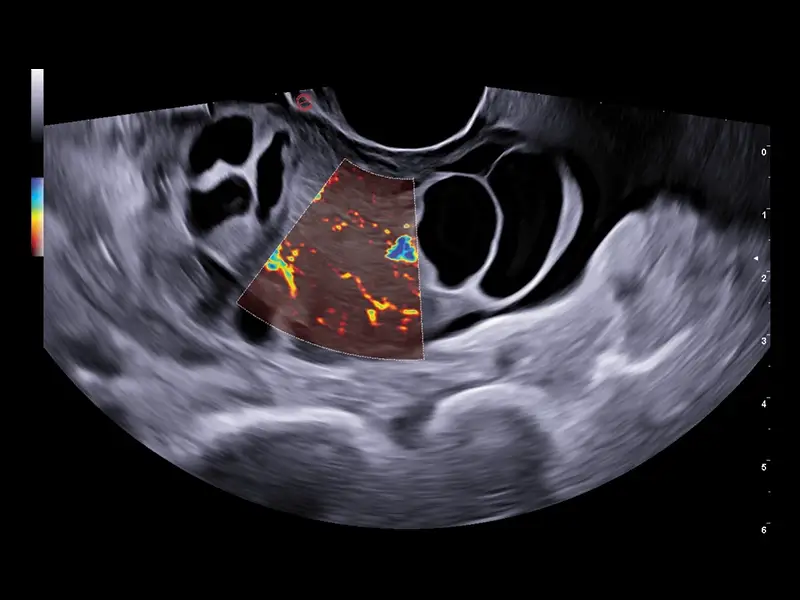

S MyLab™ A50 získáváte možnost provádět široké spektrum vyšetření, včetně jater, srdce, gynekologie a porodnictví, cév, prsu, štítné žlázy, muskuloskeletálního systému, urologie a pediatrie.